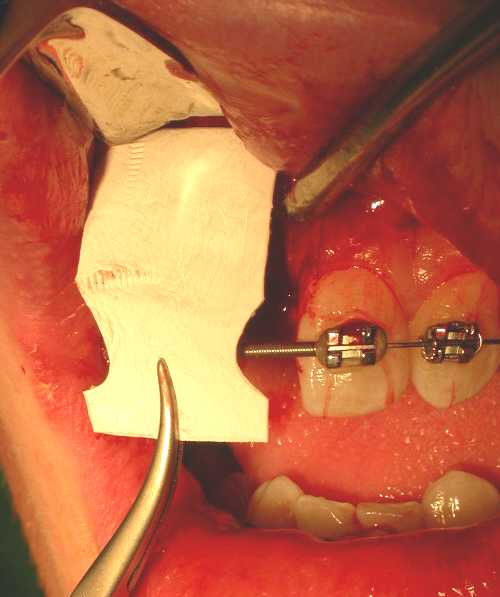

These threads can also be covered by bone harvested by a surgical filter or bone substitute. Semipermeable membrane covering this can promote healing by guided tissue regeneration (Figure 9). A cover screw is fitted over the internal threads of the implant (Figure 10) and the wound closed. The patient is advised not to wear their prosthesis for 7 to 10 days, followed by occasional wear only.

Figure 9: Material used for guided tissue regeneration.